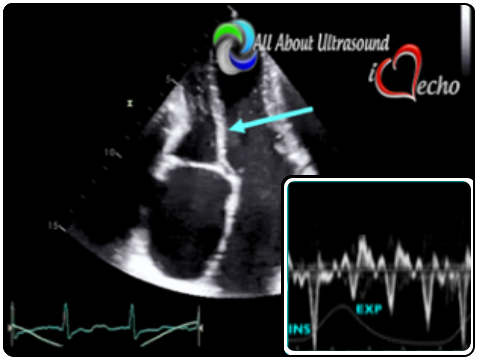

Mastering Constrictive Pericarditis CME Course

This online e-course is for sonographers interested in learning and reviewing correct techniques for performing echocardiography imaging and evaluation of constrictive pericarditis.

•Review constrictive pericarditis vs. tamponade